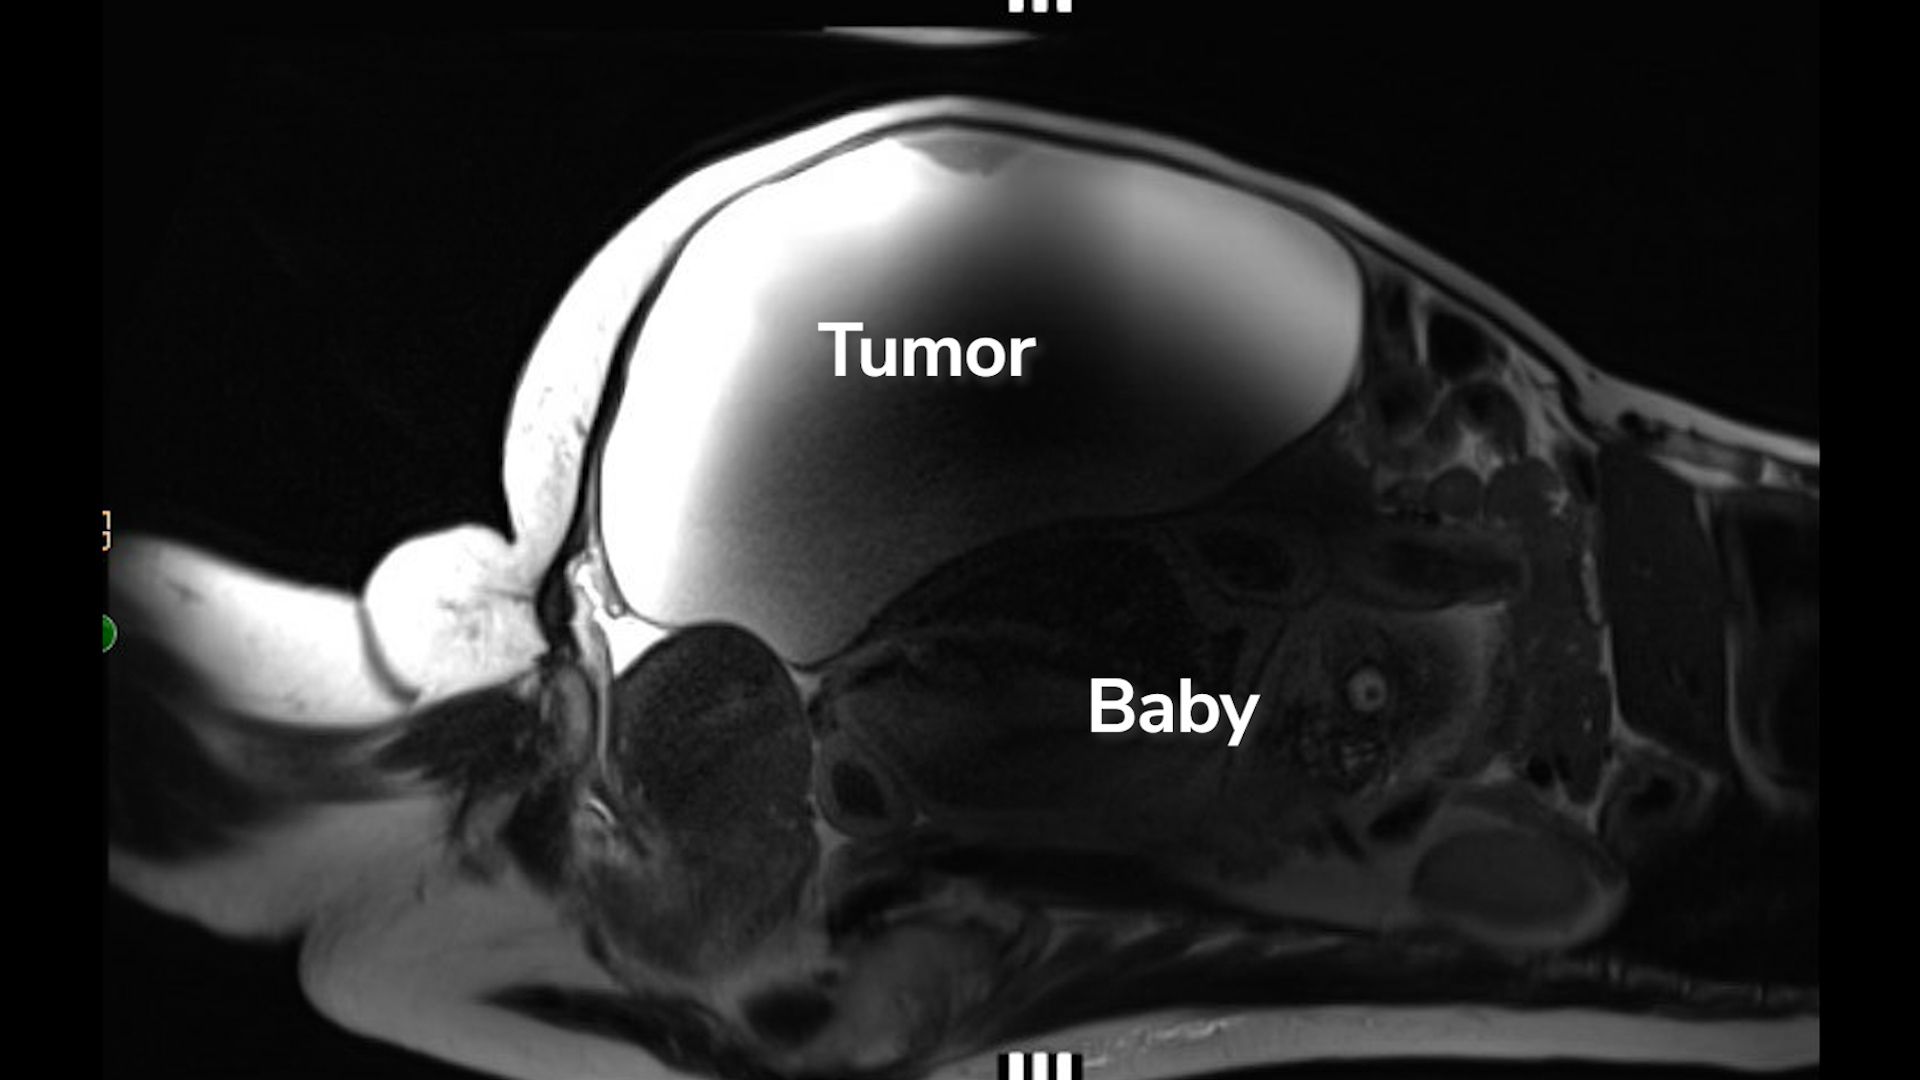

Bác sĩ qua siêu âm phát hiện thai nhi nằm ngay phía dưới khối u nang buồng trứng khổng lồ của người phụ nữ (Nguồn ảnh: Cedars-Sinai)

Tại đây, các bác sĩ phát hiện huyết áp của Lopez tăng cao bất thường. Sau khi tiến hành xét nghiệm máu, chụp MRI và siêu âm, họ xác định đây là một trường hợp thai ngoài tử cung ở ổ bụng cực kỳ hiếm. Thai nhi nằm gần gan, phần lưng tựa lên tử cung.